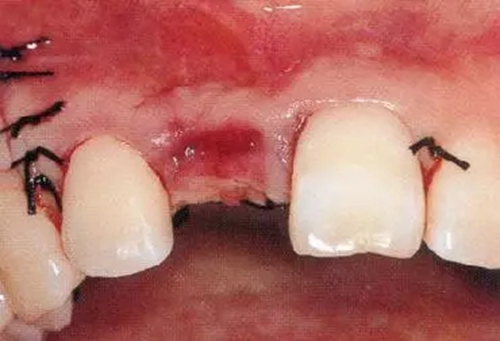

▲圖44-12,13

圖44-12 種植體植入4個(gè)月后。二次手術(shù)時(shí)同時(shí)進(jìn)行結(jié)締組織移植(CTG),以增大牙齦。

圖44-13 二次手術(shù)后的狀態(tài)。